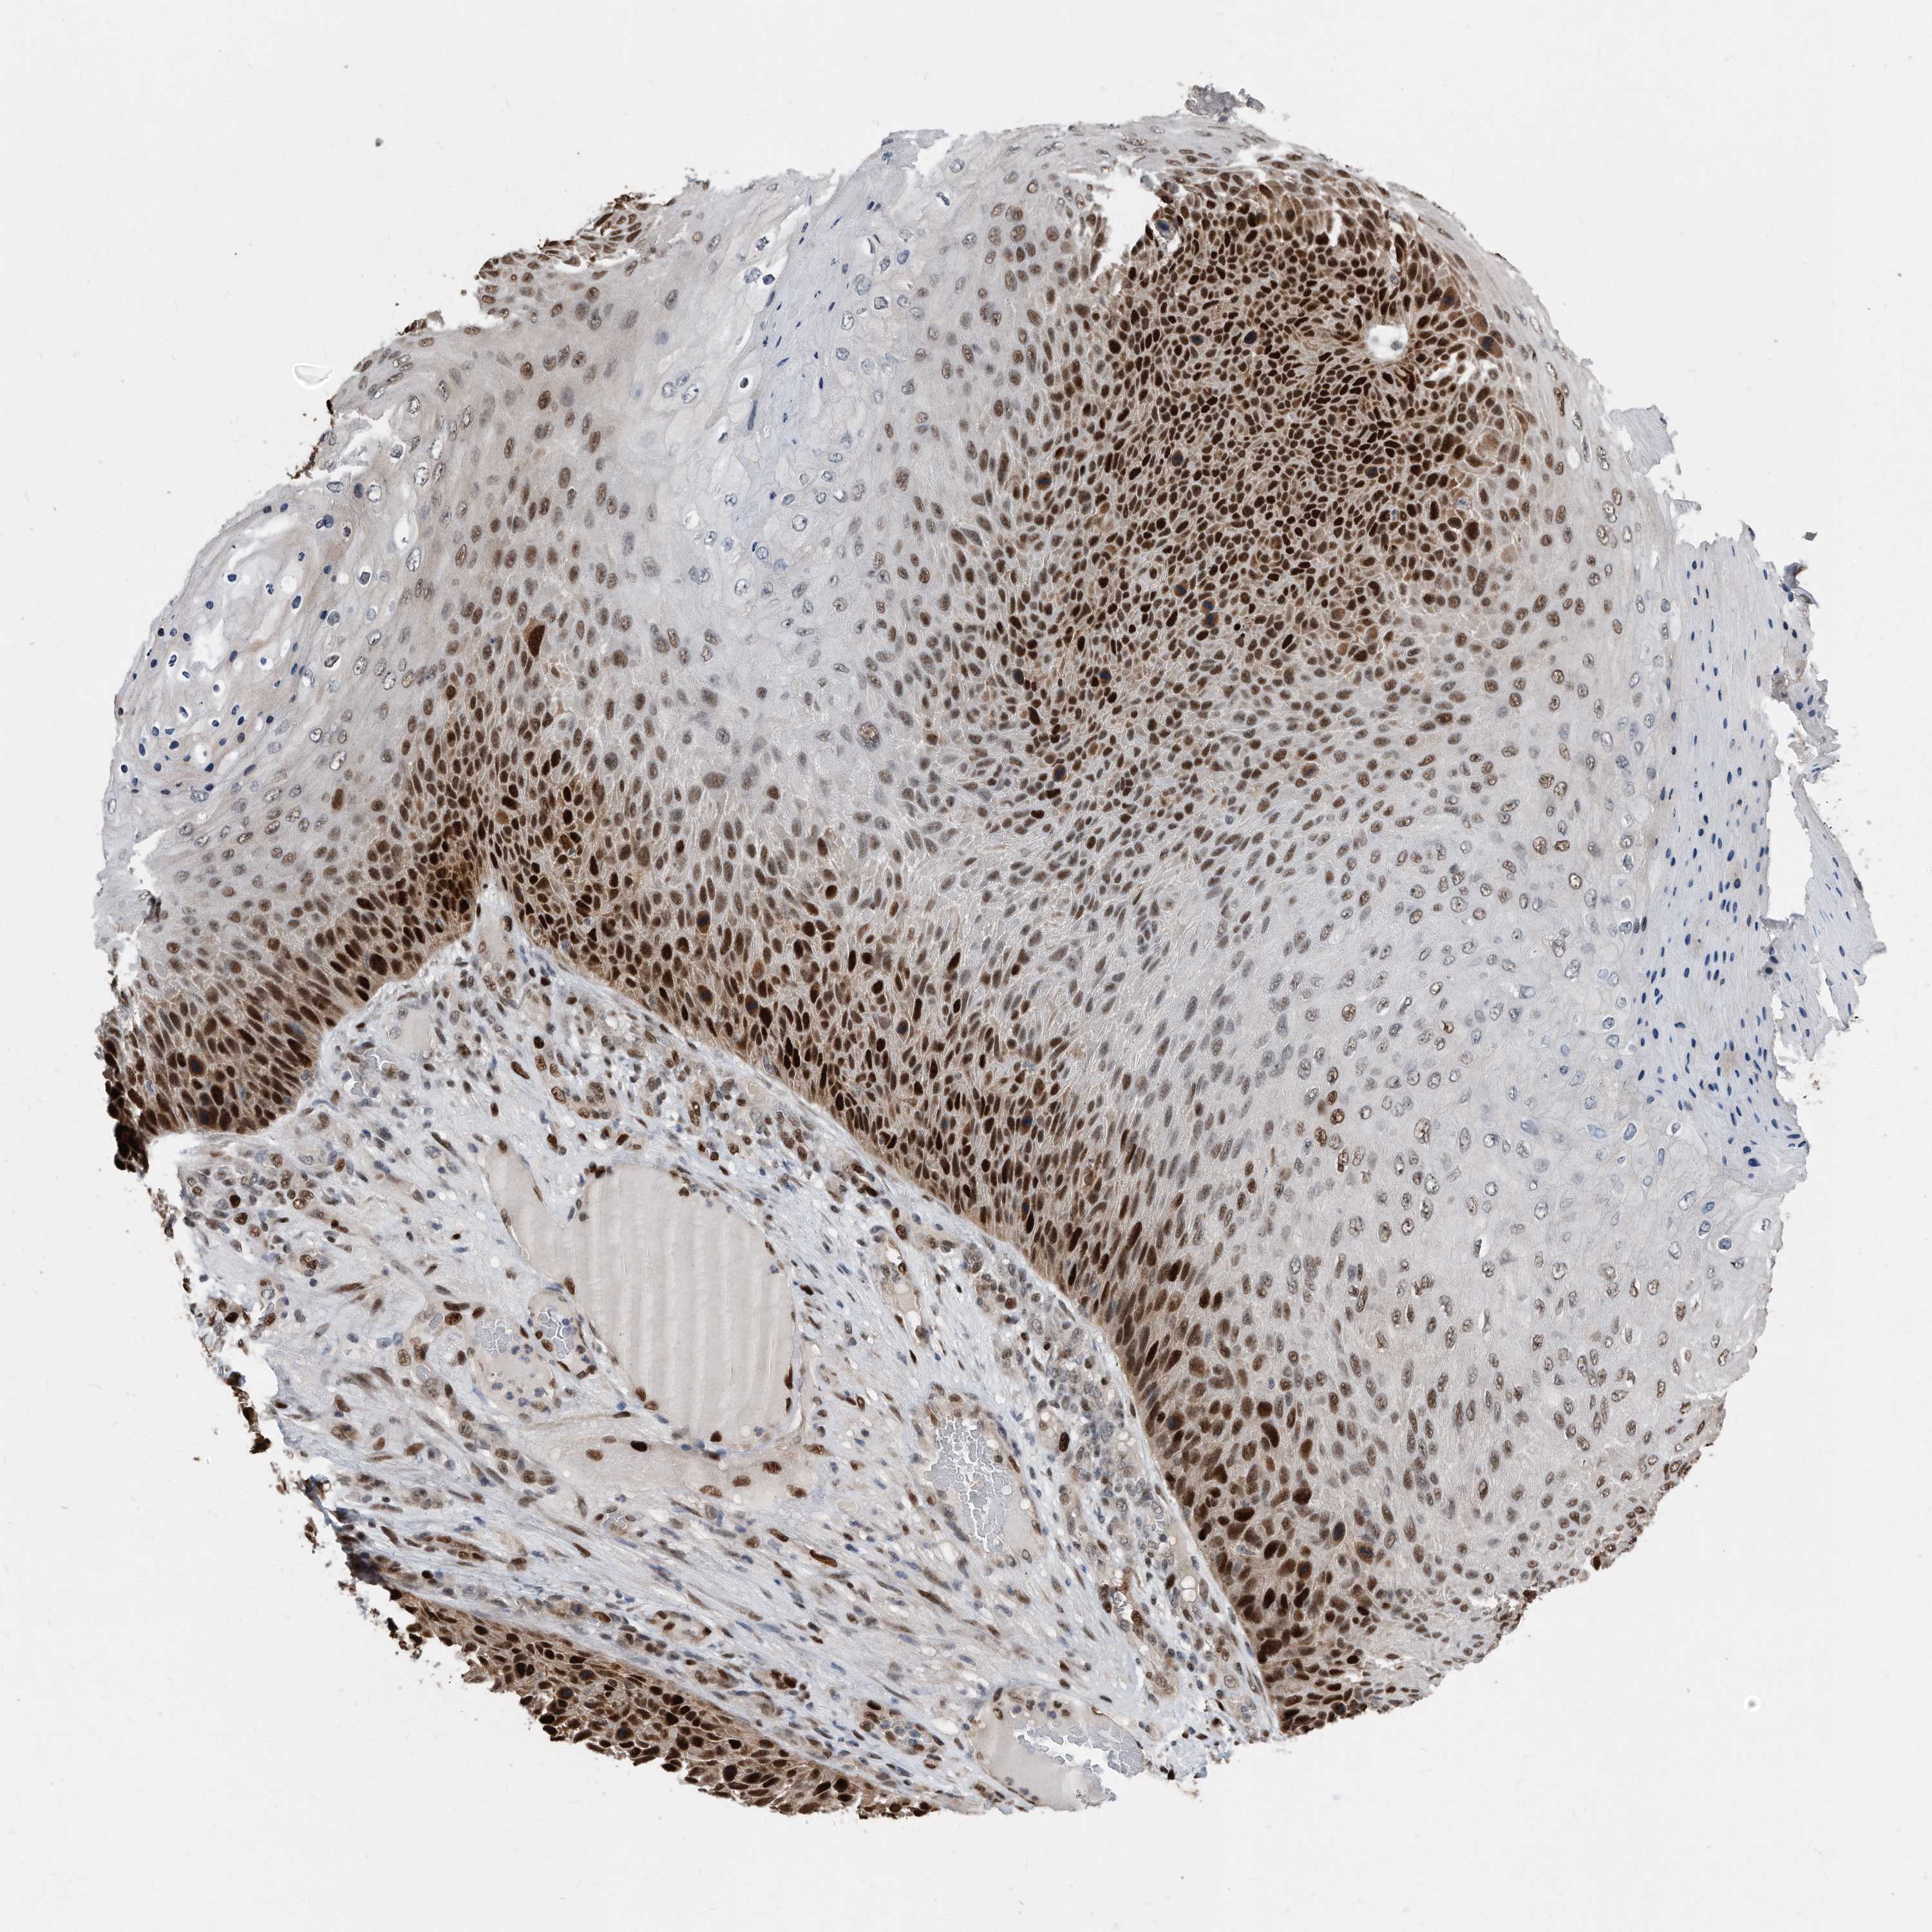

SKIN CANCER - Protein expressioni

A mouse-over function shows sample information and annotation data. Click on an image to view it in a full screen mode. Samples can be filtered based on level of antibody staining by selecting one or several of the following categories: high, medium, low and not detected. The assay and annotation is described here.

Each image is clickable and will lead to virtual microscopy that enables deeper exploration of all samples and also displays staining intensity scores, fraction scores and subcellular localization as well as patient and tissue information for each sample.

HPA030521

HPA030522

HPA030523

CAB000148

CAB080240

CAB080241

CAB080242

Staining

High

Medium

Low

Not detected

Intensity

Strong

Moderate

Weak

Negative

Quantity

>75%

75%-25%

<25%

None

Location

Nuclear

Cytoplasmic/membranous

Cytoplasmic/membranous,nuclear

Basal cell carcinoma

Squamous cell carcinoma, NOS

Squamous cell carcinoma, metastatic, NOS